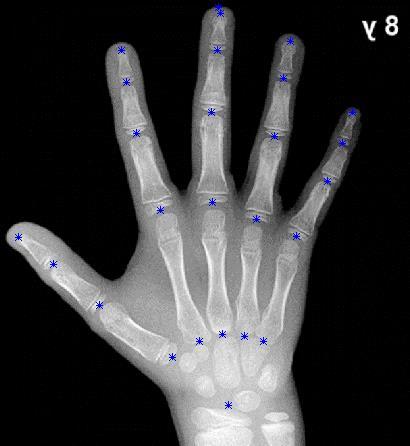

Figura 12. Carpograma de referencia con adición de puntos de análisis 24

Teniéndose el carpograma de referencia, se importa dicha imagen a SolidWorks, con el fin de realizar el análisis de dimensiones correspondiente. Primero se determinan los puntos de análisis para cada hueso de la mano, acorde a las recomendaciones dadas en “Hand Bone Age A Digital Atlas of Skeletal Maturity”, obteniéndose una imagen con puntos de referencia (Figura 12).

Posteriormente, se extienden líneas entre los puntos de análisis para cada una de las cadenas cinemáticas que componen la mano, esto con el fin de aproximar la imagen del carpograma de referencia a la representación esquemática planteada anteriormente (Figura 10), y así poder dimensionar la representación esquemática. Una vez hecho esto, se obtiene la imagen que se observa en la Figura 13.